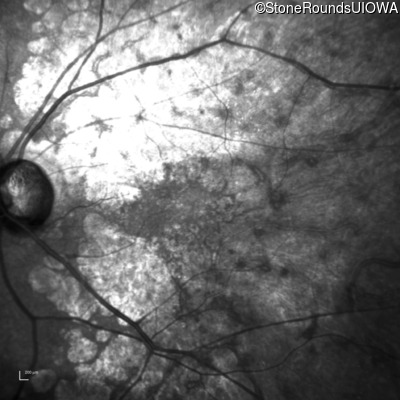

This 81 year old man began using a flashlight to read menus in his 40's. At age 75 his ophthalmologist noticed abnormal fundus findings and referred him to a retina specialist.

| Late Onset Retinal Dystrophy | C1QTNF5 | Ser163Arg AGC>AGA | AD |